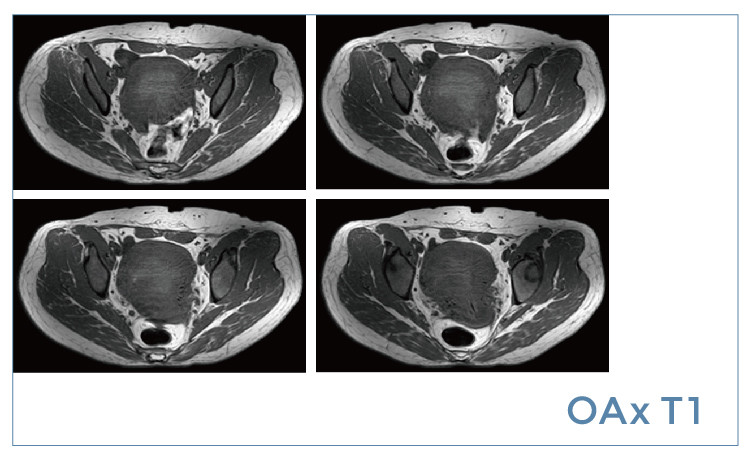

【朗润影像档案】20190621磁共振影像病例结果讨论